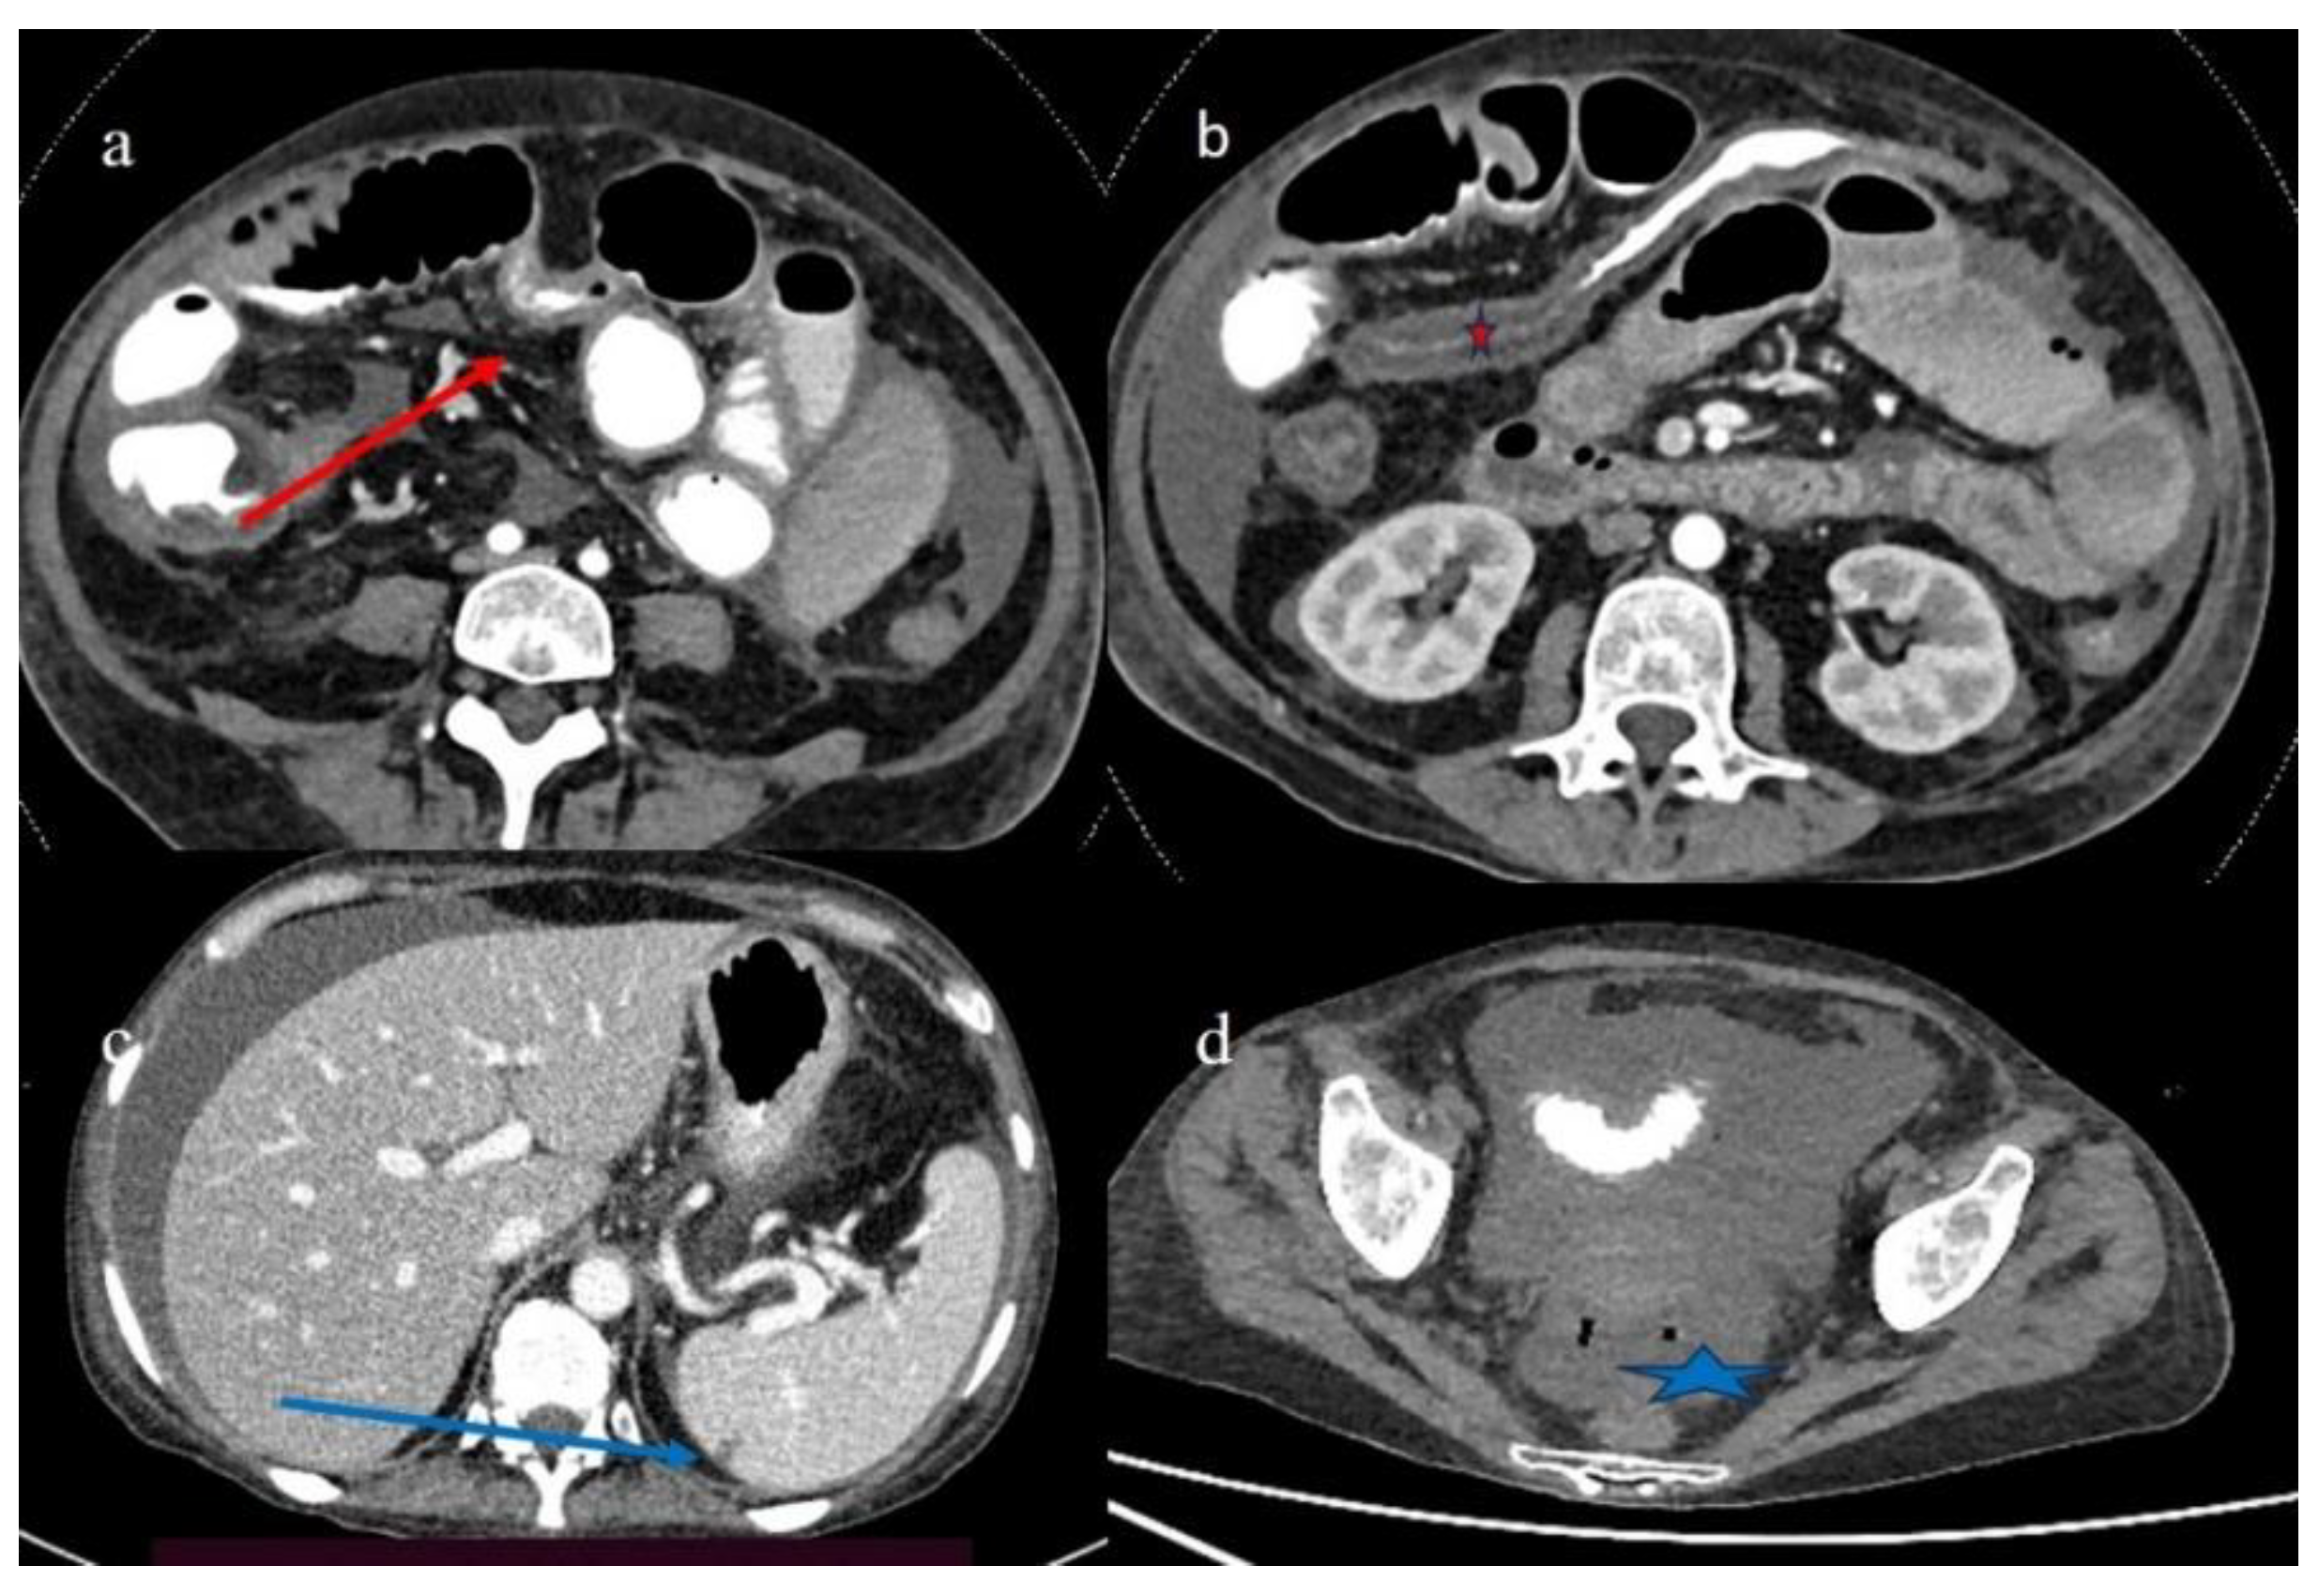

| 4 | P | P | Intestinal diffuse homogeneous thickness with homogeneous mucosal enhancement (on CECT control at 66 days after the HSCT); diffuse small bowel involvement with increased parietal thickness on CECT control at 120 days | Appearance of multisegmental thickness on sigma and descending colon and stratified enhancement on transverse colon on the CT FU at 120 days | Diffuse comb sign and poor reactive mesenteric lymph node | Mild gallbladder thickness and persistence of biliary tract dilatation on follow-up CT |

| 5 | P | P | Multisegmental thickness with stenosis on jejunal loops and SBO and segmental and focal thickness on the terminal ileus and appendix | Diffuse parietal thickness with stratified enhancement | Mild comb sign, poor reactive mesenteric lymph node, small air bubbles in the ascites | Small splenic areas of ischemia |